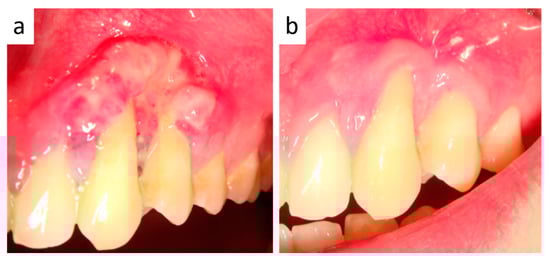

2. Case Presentation